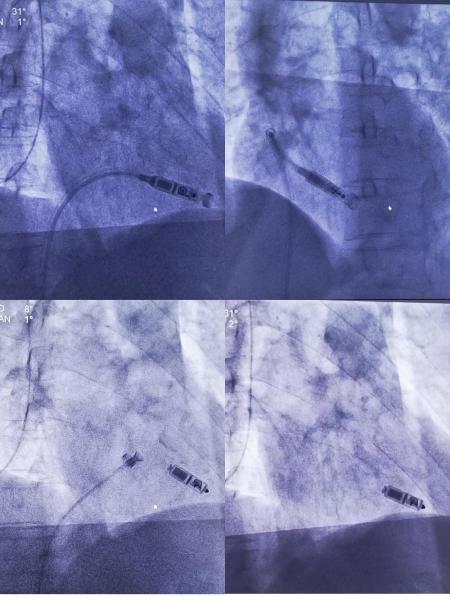

2月27日,湘西州人民医院心内三科成功完成湘西州首例Micra无导线起搏器植入手术,手术顺利,Micra一次释放成功,参数正常,手术耗时仅30分钟。此次手术的成功开展,开启了湘西州“无线起搏时代”,标志着我院心脏起搏器植入技术达到国内先进水平。

术中,穿刺右股静脉,通过27F血管鞘将Micra无导线起搏器送到右室低位间隔部,释放Micra后确认至少2个钩齿钩住心内膜,测试各种参数满意,手术圆满结束。